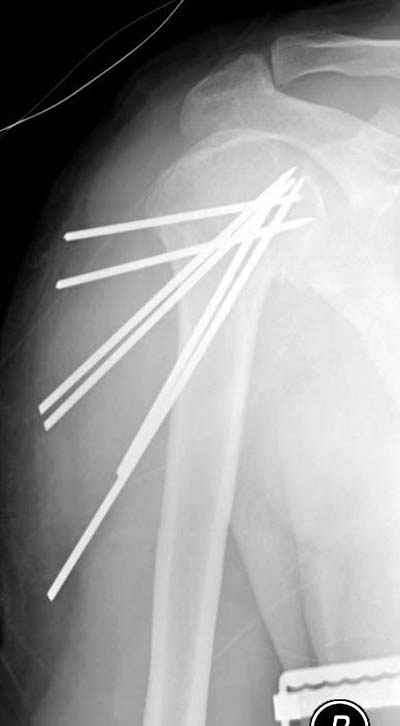

Женя, а как ты водишь спицы, в смысле, как делаешь входное отверстие, и как в него проводишь V-спицу? А то о дна из спиц, та, у которой не дошла до головки одна палочка буквы V, как-то выглядит на рентгенограмме, как будто или через очень большое отверстие введена, или каждая половинка через отдельные отверстия.

Мне кажется, проблема в том, что не все концы спиц зашли в головку, и зашедшие - недостаточно далеко прошли.

Спицы провожу по передней и задней поверхностям плечевой кости через 4,5 мм отверстия на разных уровнях.

Идеей презентации случая была демонстрация важности постоп Рг - хотя казалось бы все было сделано под флюороскопическим контролем и интраоперационно подозрений на нестабильность не возникло, а такая вот

неожиданность...

Уточни - обе части буквы V вводишь в одно отверстие? А то по снимкам выглядит, что в разные.

V-спица проводится через 4,5 мм отверстие. Видимо, из-за разной длины вторая половина спицы *пролетела* мимо отверстия, что и привело к вторичному смещению костных фрагментов.